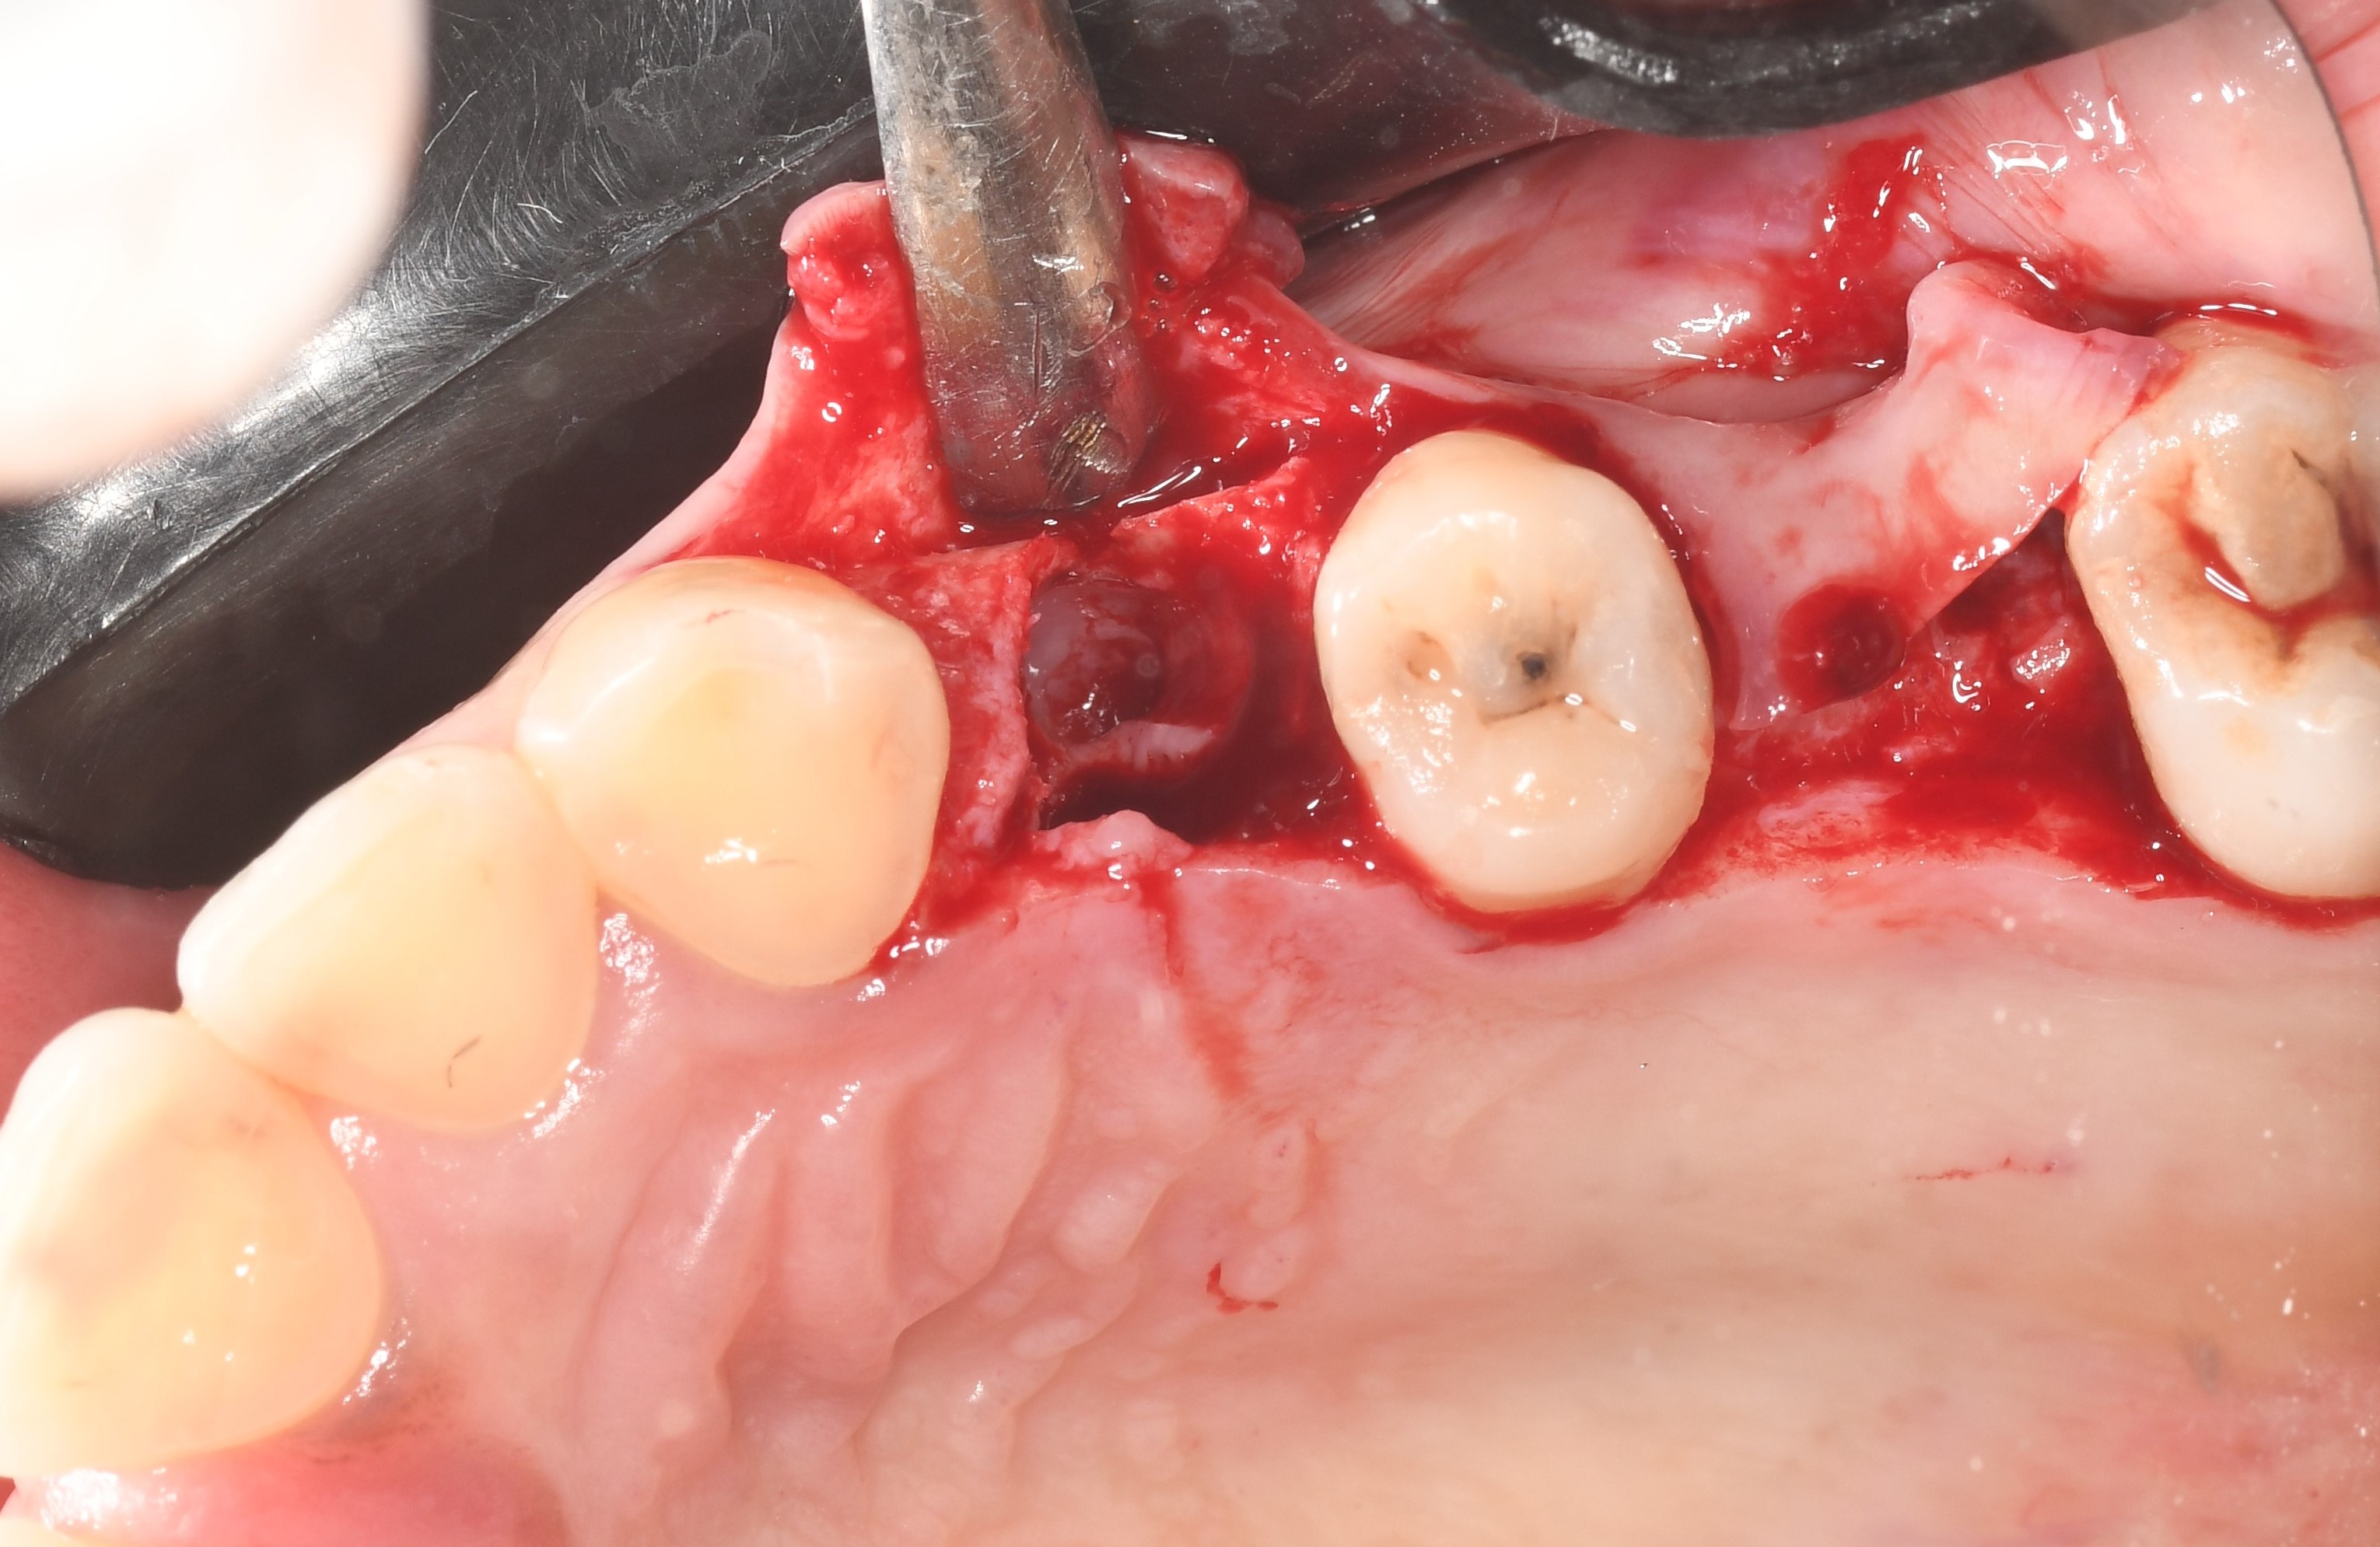

Initial situation:

After the teeth extraction, a bone defect and a different angle are revealed, and the implantation cannot be completed.